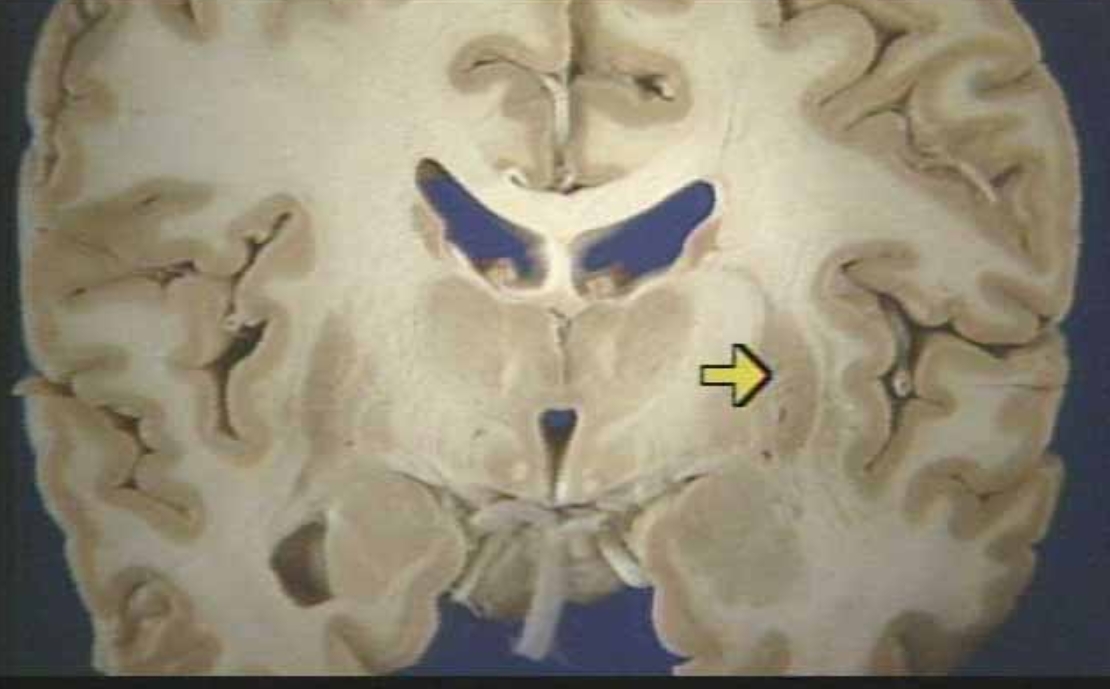

What is the arrow pointing at?

Hippocampus